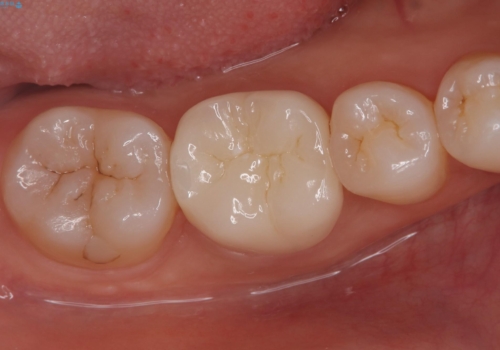

術後1年経過を見ていますが、問題なく良好な経過をたどっています。

オールセラミッククラウン(スタンダード)11万円